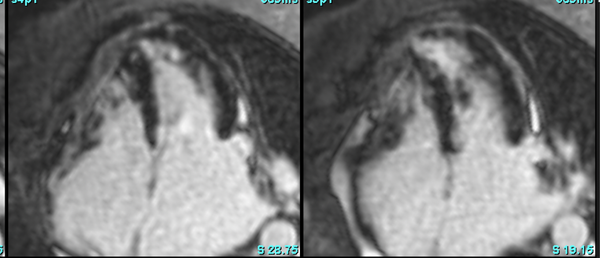

Infarcts

Aneursym